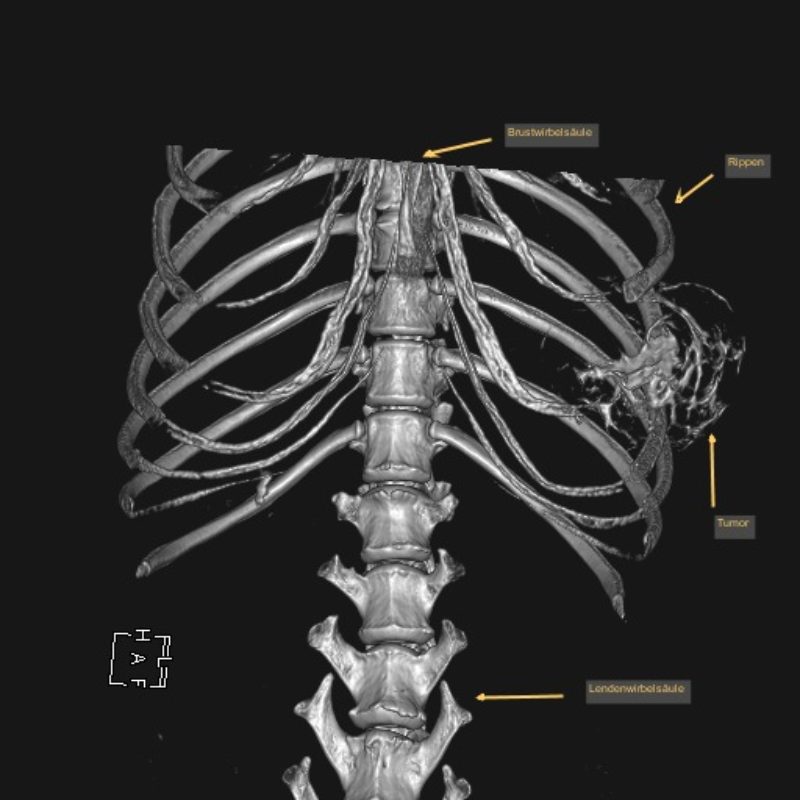

Leo wurde nun nach einer gründlichen allgemeinmedizinischen sowie labortechnischen Untersuchung zur Computertomographie (CT) angemeldet, die in Vollnarkose stattfinden muss. Mit dieser Technik werden mit Hilfe von Röntgenstrahlen ein Millimeter dünne Schichtaufnahmen angefertigt und damit das genaue Ausmaß des Tumors dargestellt. Zum anderen kann im Vergleich zu einem konventionellen Röntgenbild eine überlagerungsfreie Aussage über den Zustand des benachbarten Weichteilgewebes getroffen werden. Diese Informationen sind für den Chirurgen unumgänglich, damit er die Operation planen kann.

In diesem Fall wurde durch die CT das enorme Ausmaß der Umfangsvermehrung deutlich, sodass insgesamt drei Rippen inklusive der dazwischenliegenden Muskeln in Mitleidenschaft gezogen wurden. Die gute Nachricht war, dass der innerhalb der Bauchhöhle unmittelbar anliegende linke Leberlappen, Magen und Milz sowie der hintere Anteil des linken Lungenflügels im Brustkorb noch nicht vom Tumorwachstum erfasst waren.